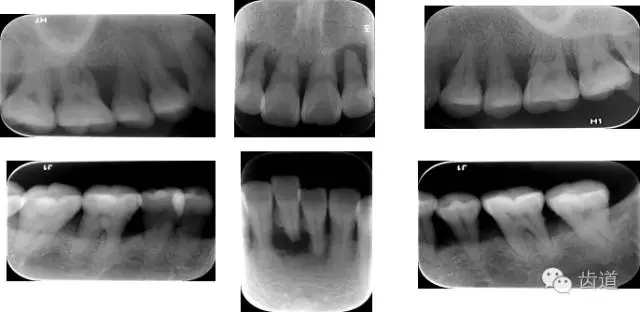

X線:根尖片、曲面斷層片(牙槽嵴頂,水平垂直吸收,程度)

21.webp.jpg

22.webp.jpg

23.webp.jpg